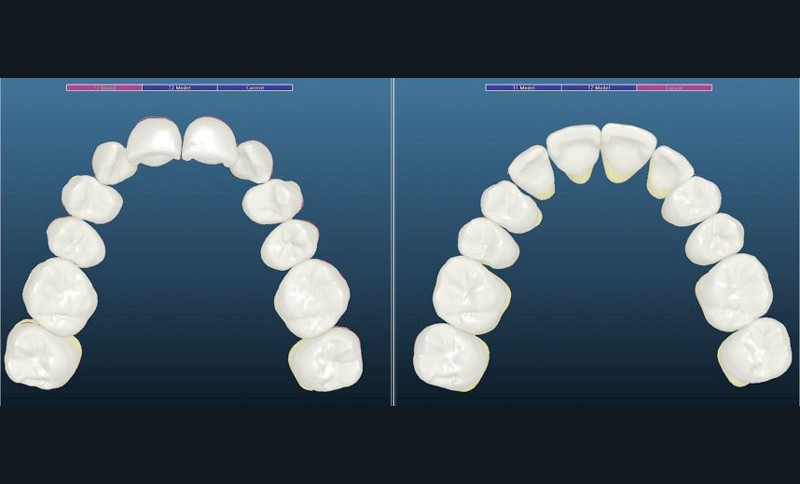

Un appareillage Damon métal a été mis en place, réalisé à partir d’un set up numérique Insignia pour obtenir un contrôle précis des torques et de la forme d’arcade et réduire le temps de finition grâce à un collage indirect très précis.

L’objectif, en utilisant la technique Insignia est de réduire le temps de traitement de 28 à 18 mois avec 12 rendez-vous (fig. 5 à 14).

Les objectifs de traitement ont été remplis. Nous avons observé un excellent contrôle du torque et une absence de perte de l’occlusion postérieure grâce à la technique Insignia.